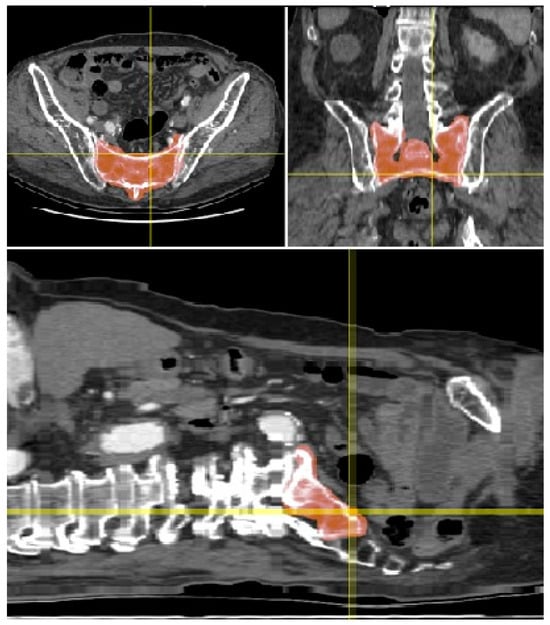

- To support the translational relevance of the proposed technique in a clinical illustration case, we included intraoperative and postoperative imaging from a representative patient with a B-type pelvic injury. The patient underwent standard percutaneous sacroiliac screw fixation. A lateral fluoroscopic image was obtained intraoperatively after guidewire placement, and postoperative CT scans (sagittal and axial) were acquired routinely.

3.4. Preliminary Clinical Illustration

4.3. Pilot Application in Surgery